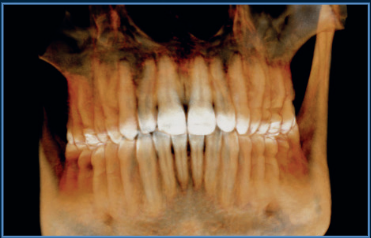

Our flagship high resolution tomograph delivers cutting-edge image quality that allows you to visualize anatomy and pathology beyond traditional CBCT standards. This comes from its unique flat panel detector (FPD), which provides an industry-smallest, 0.2mm focal spot. Investing in the Excelsior ENDO mean offering patients superior diagnostics and setting a practice apart as a leader in dental imaging.

The powerful system components of the PreXion Excelsior Endo enable an extraordinary combination of the most precise 3D imaging, large image detail, lowest radiation exposure, reliable diagnostics and digital planning, which is optimized specifically for endodontic diagnostics and treatment with its flat panel detector (FPD) providing an industry-leading 02.mm focal spot. Its patient management system is designed for secure and networked communication of patient data across multiple rooms within a practice and can be integrated into the existing infrastructure with ease.

PreXion Excelsior ENDO has outstanding resolution with Isotropic Voxel size as low as 48um.